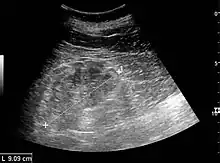

Ultrasound

Kidney ultrasonography is useful for diagnostic and prognostic purposes in chronic kidney disease. Whether the underlying pathologic change is glomerular sclerosis, tubular atrophy, interstitial fibrosis, or inflammation, the result is often increased echogenicity of the cortex. The echogenicity of the kidney should be related to the echogenicity of either the liver or the spleen (Figure 22 and Figure 23). Moreover, decreased kidney size and cortical thinning are also often seen and especially when disease progresses (Figure 24 and Figure 25). However, kidney size correlates to height, and short persons tend to have small kidneys; thus, kidney size as the only parameter is not reliable.[54]

Chronic renal disease caused by glomerulonephritis with increased echogenicity and reduced cortical thickness. Measurement of kidney length on the US image is illustrated by '+' and a dashed line.[54]